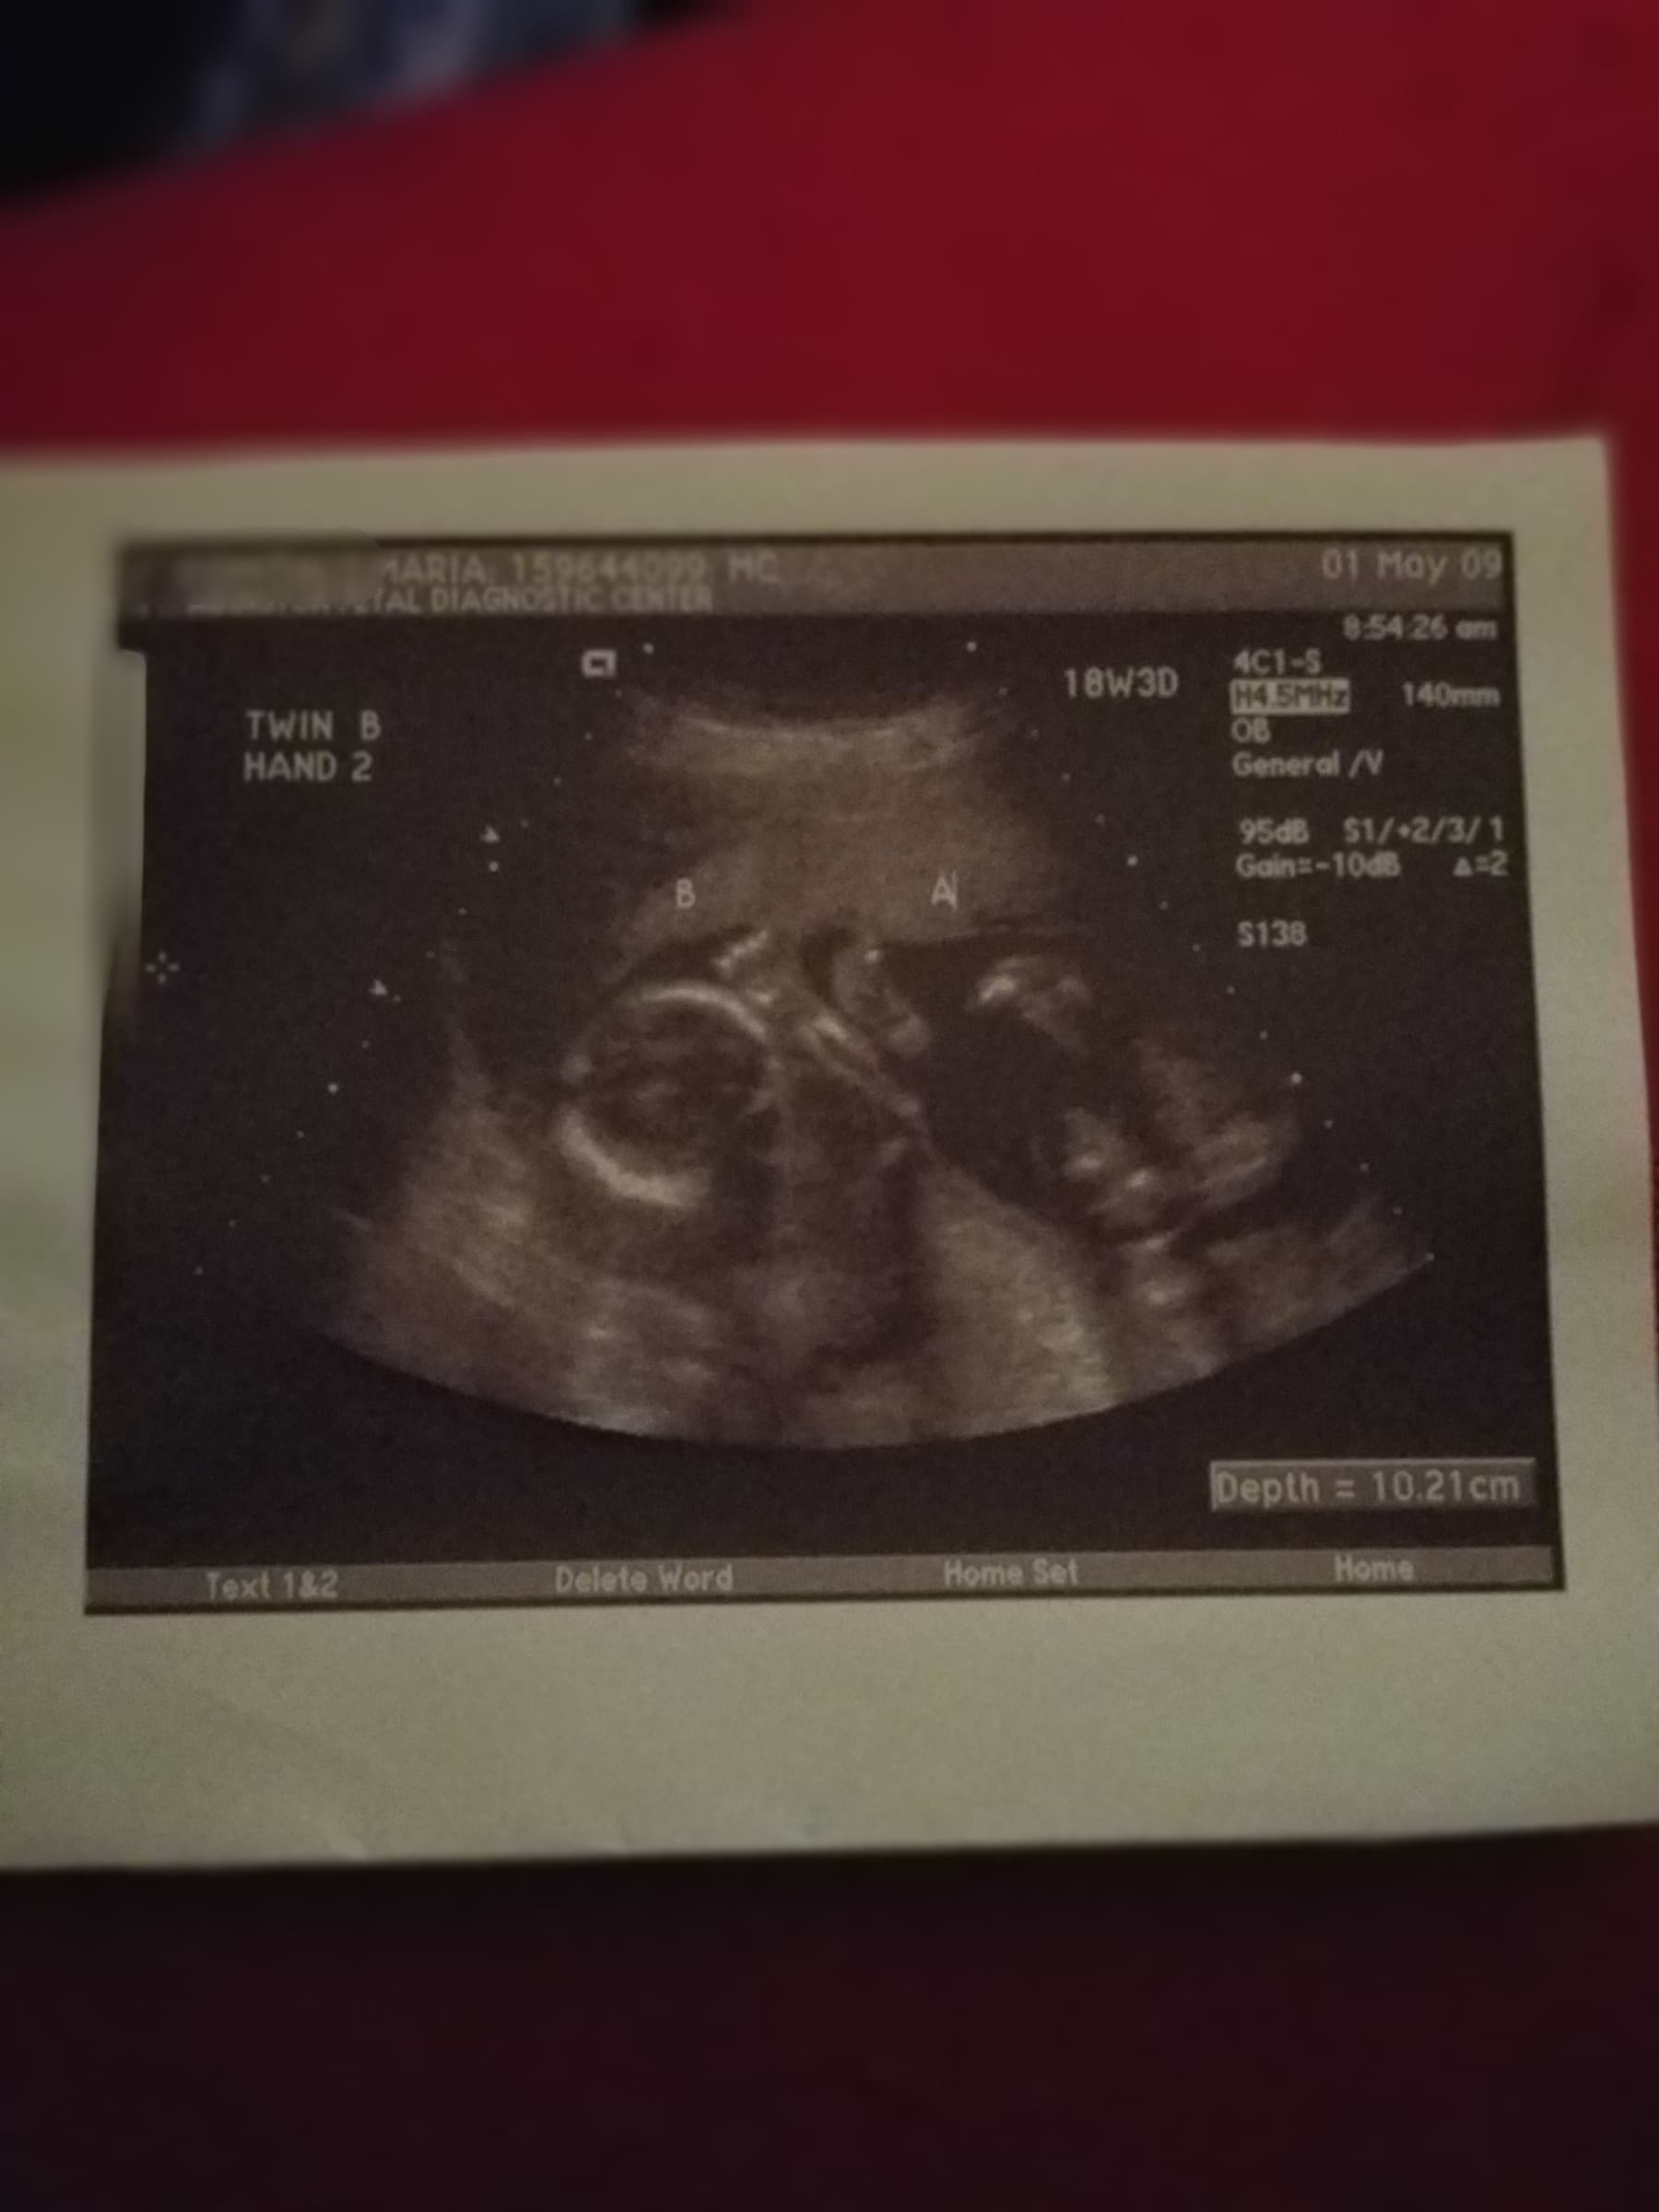

Ultrasound Photos at 18 Weeks Pregnant With Twins